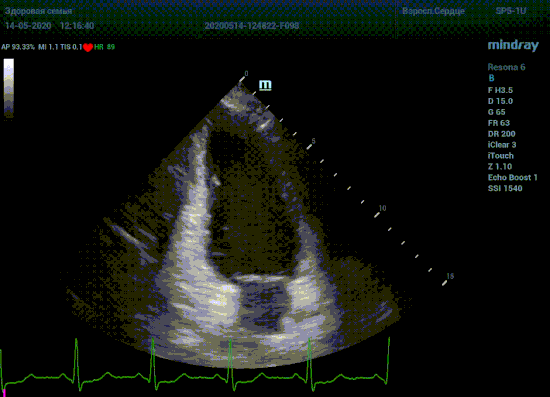

С появлением В режима реализовалась возможность визуализации всех сегментов миокарда из парастернальных и апикальных сечений. Метод Teicholtz в широкой практике сменился методом дисков. Метод дисков, или метод Simpson, позволяет разбить левый желудочек на 20 дисков, с расчетом объема каждого из них. Используя 2 перпендикулярных сечения, апикальные двух и четырех камерное, мы приближаемся к значению реального объема левого желудочка. Исследователь обводит интерфейс эндокард – кровь в фазу диастолы и фазу систолы. Линия простирается от кольца митрального клапана и до кольца митрального клапана, четко разграничивая объем желудочка от предсердия. Для достоверного изменения необходимо использовать ЭКГ канал.

Что могут предложить современные приборы? Приборы нашего времени являются мощными вычислительными машинами, способными обрабатывать полученную информацию даже без помощи человека. Система автоматического вычисления фракции выброса – AUTO EF на приборах серии Resona компании Mindray сделает все за вас. За пару секунд прибор сам отыщет нужную фазу сердечного цикла и произведёт измерение и расчеты, а также покажет график изменения объема в сердечном цикле. От Вас требуется только получить качественное 4С и 2С сечение. Впрочем, прибор всегда оставляет возможность коррекции, если доктор имеет свое мнение на расположение точек планиметрии или момента измерения по ЭКГ каналу.